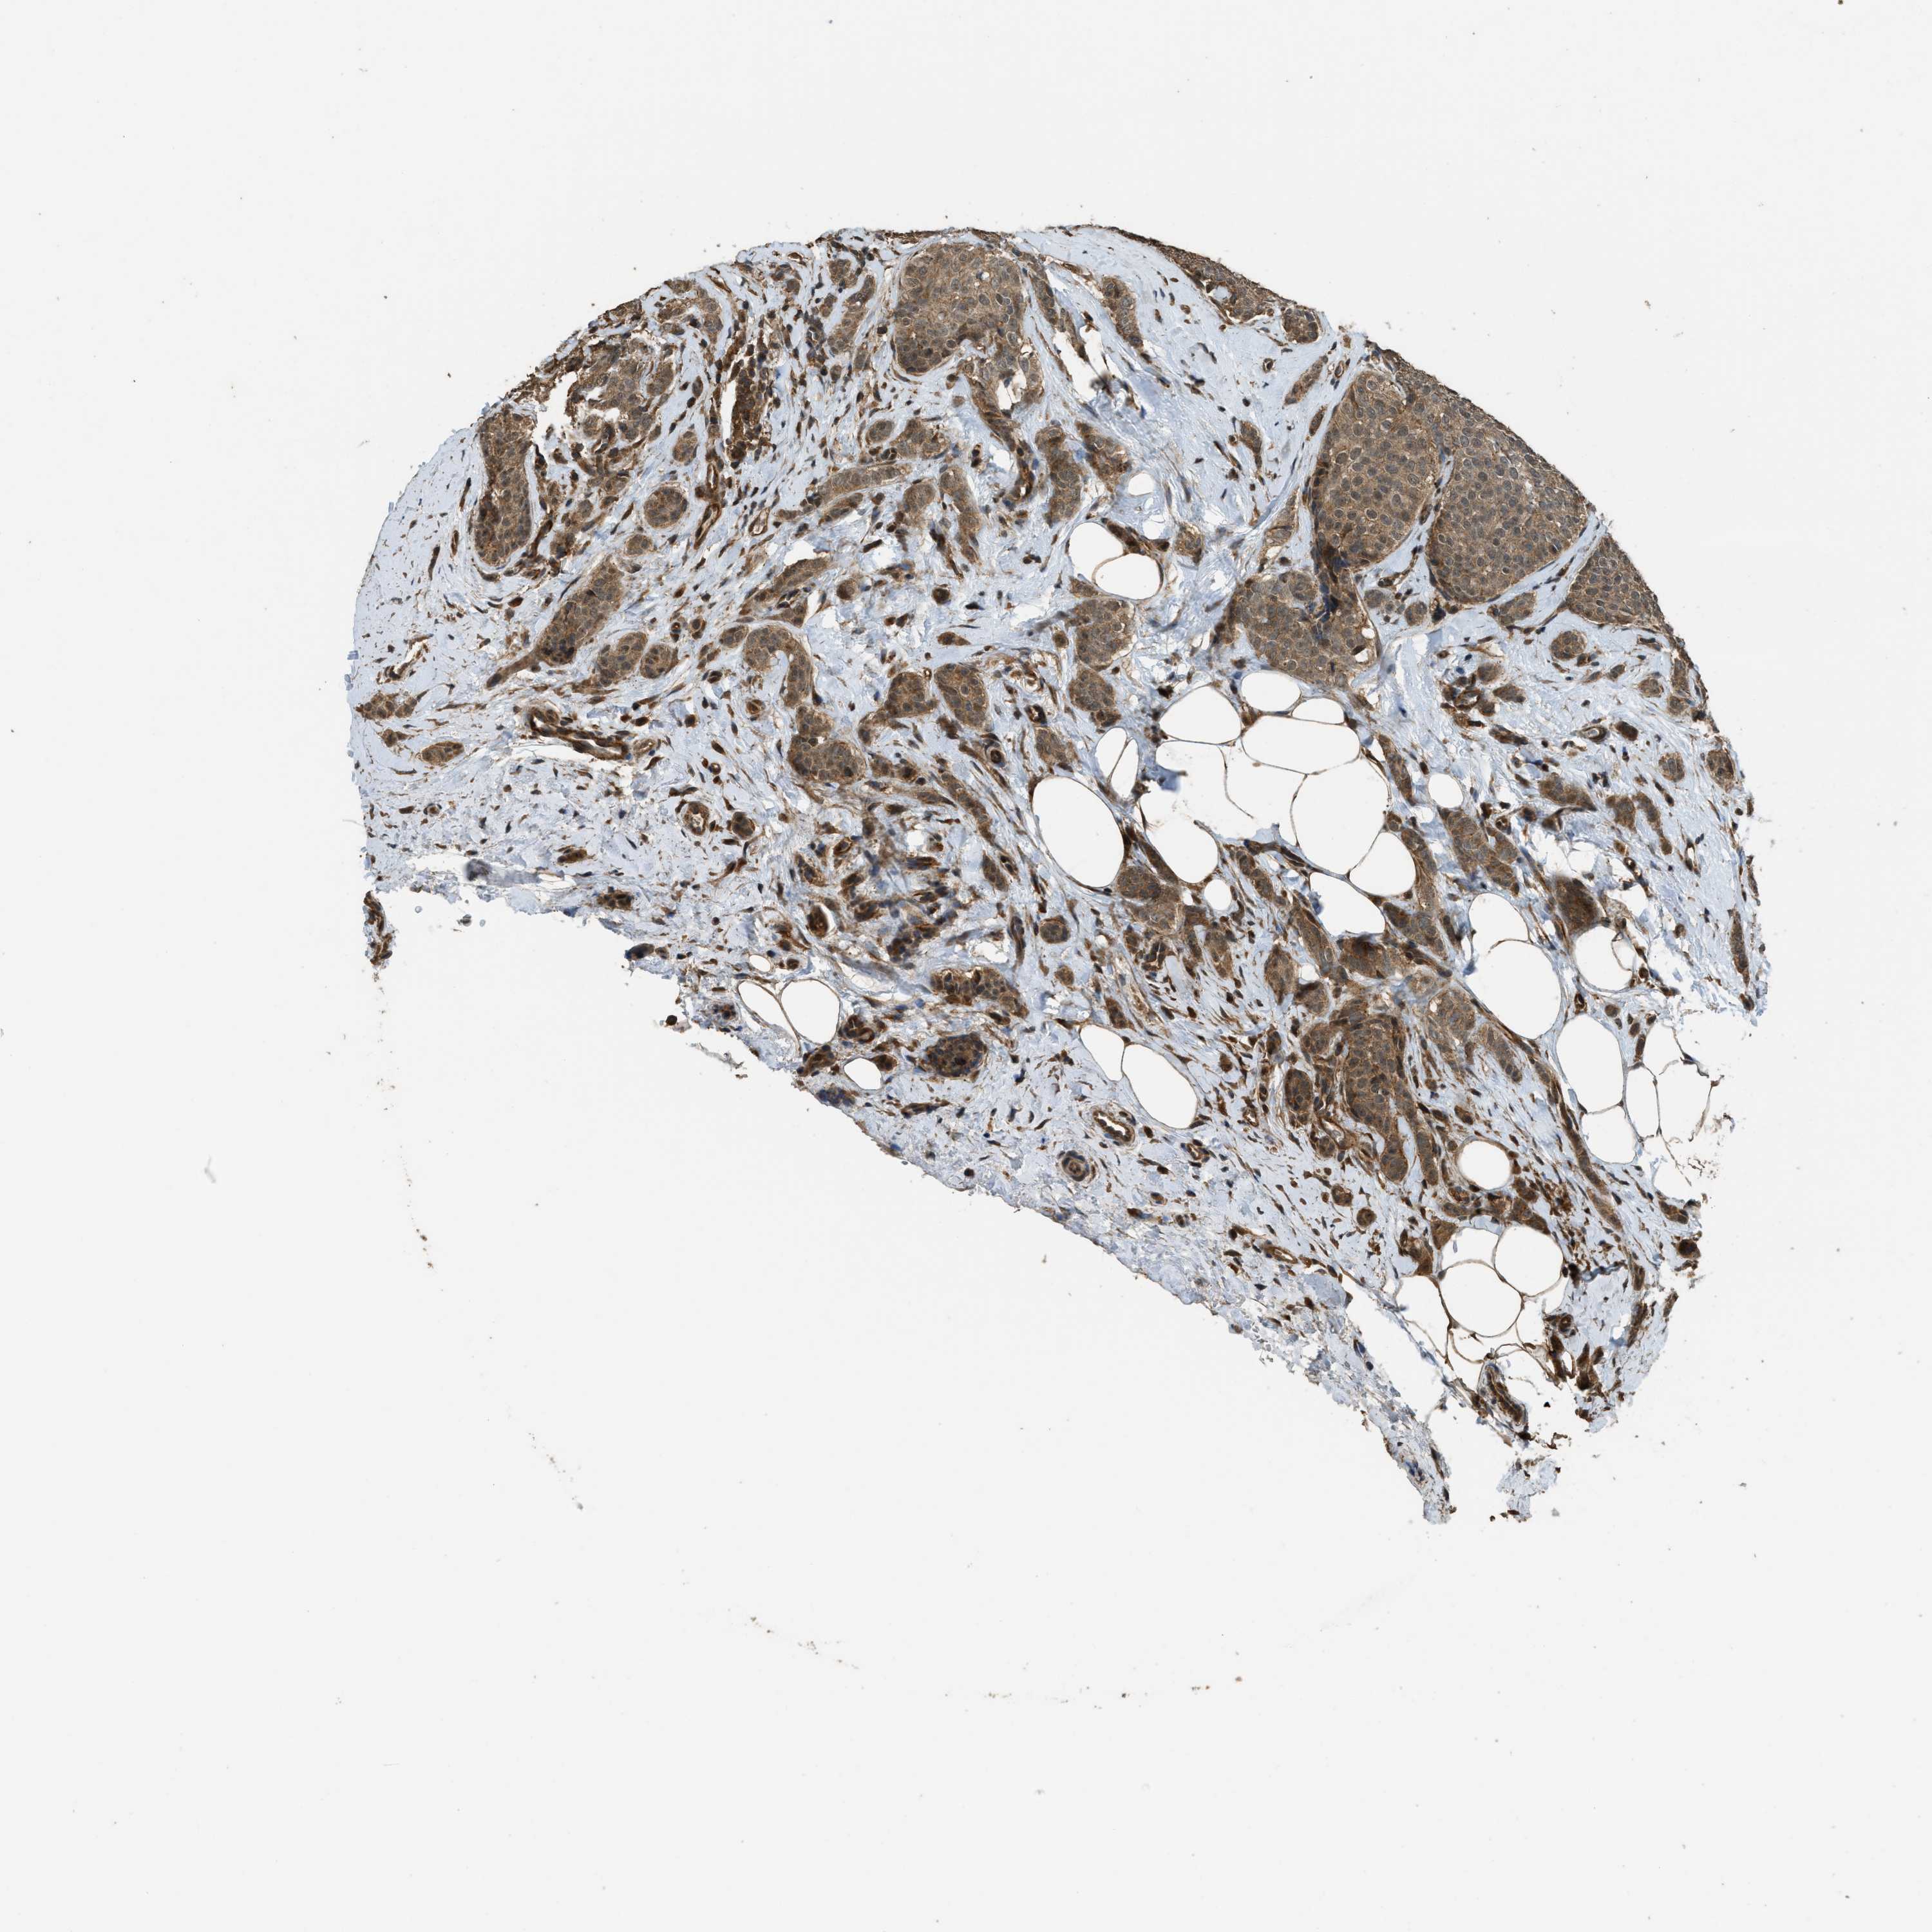

CANCER BREAST CANCER Show tissue menu

BRCA TCGA BRCA VALIDATION PROTEIN EXPRESSION